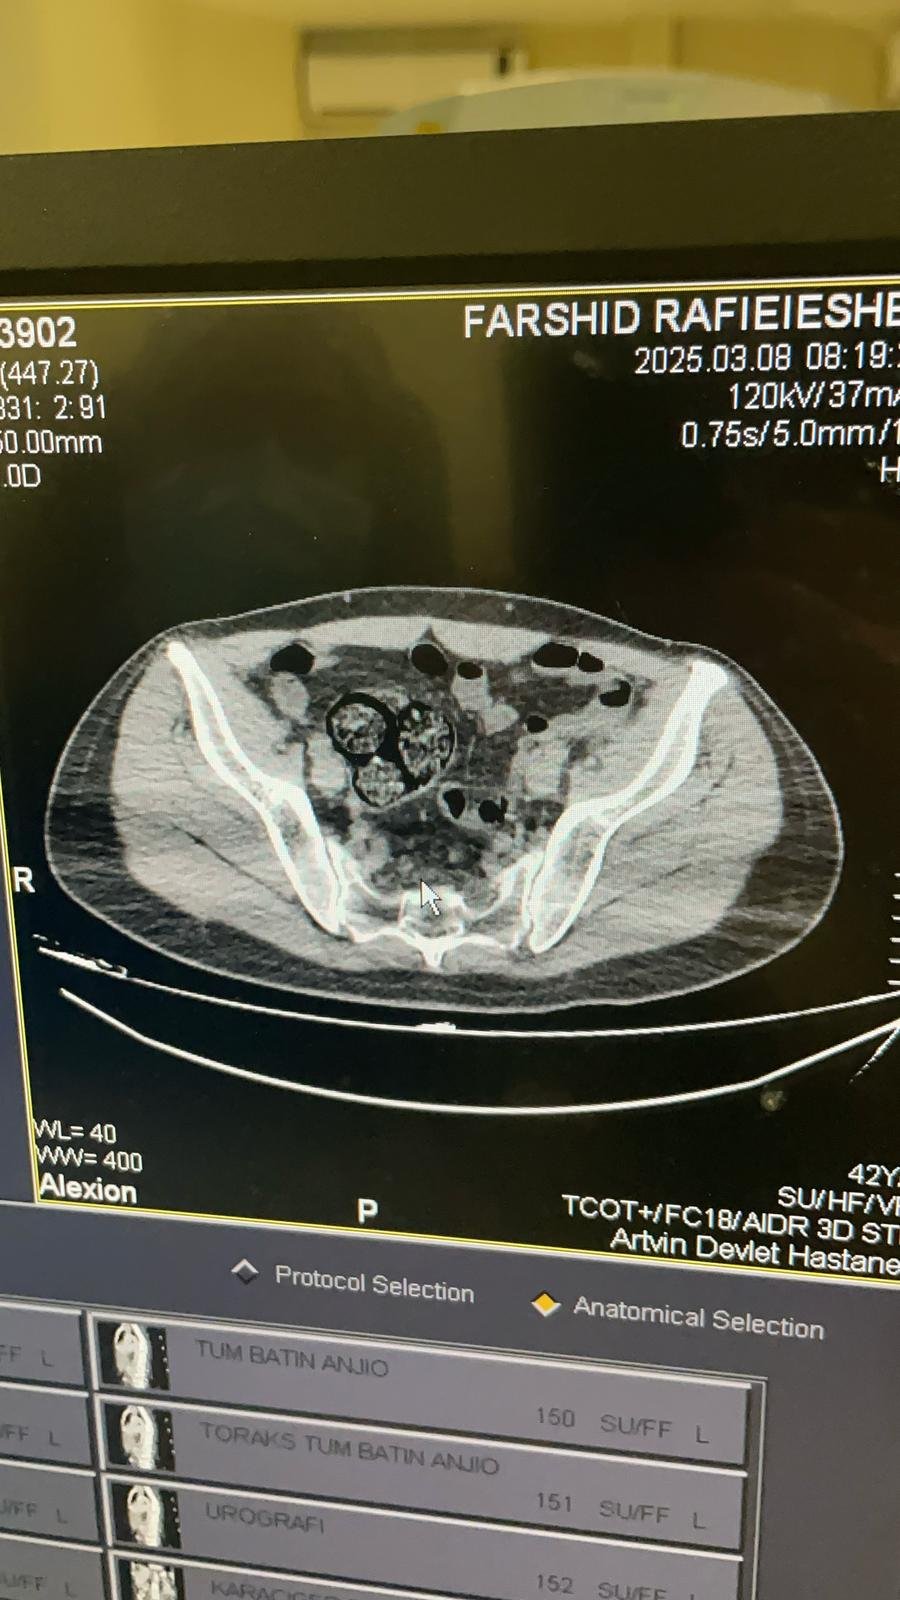

Artvin Devlet Hastanesi'nde tomografisi çekilen şüphelinin bağırsaklarında 10 paket halinde uyuşturucu madde taşıdığı belirlendi. Şüphelinin hayati tehlike oluşturabilecek şekilde sakladığı paketler, cerrahi müdahaleyle çıkarıldı.

İncelemede paketlerin içinde toplam 350 gram metamfetamin olduğu tespit edildi.